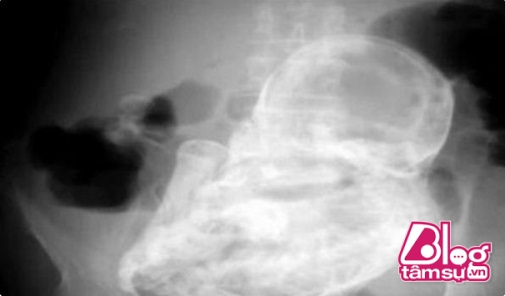

Bà lão không dám tin vào mắt mình khi nhìn tấm X-quang ghi lại chiếc bụng bầu to phình nhiều ngày của mình.

Sau thời gian dài bị đau và chiếc bụng có kích thước ngày càng tăng, người phụ nữ đã đến bệnh viện để kiểm tra. Ban đầu các bác sĩ cho rằng, người phụ nữ mắc chứng đau dạ dày mãn tính. Tuy nhiên, sự thật phía sau chỉ khi chụp X-quang mới được các bác sĩ phát hiện.

Theo những hình ảnh được chụp lại bên trong, chiếc bụng của bà lão có kích thước bất thường như vậy là do nó chứa một bào thai đã chết. Bào thai này được dự đoán đã tồn tại trong bụng của người bà lão 38 năm. Đây chính là tình trạng thai lưu mà hàng triệu người phụ nữ rất sợ hãi. Vì không kiểm tra và phát hiện kịp thời nên bào thai này đã bị chuyển biến trong cơ thể người phụ nữ.

Các bác sĩ cho rằng, bà lão phải trải qua ca phẫu thuật để có thể loại bỏ bào thai đã chết này trong cơ thể. Chắc chắn sức khỏe của bà lão cũng bị ảnh hưởng ít nhiều vì khối u đã tồn tại khá lâu trong cơ thể.